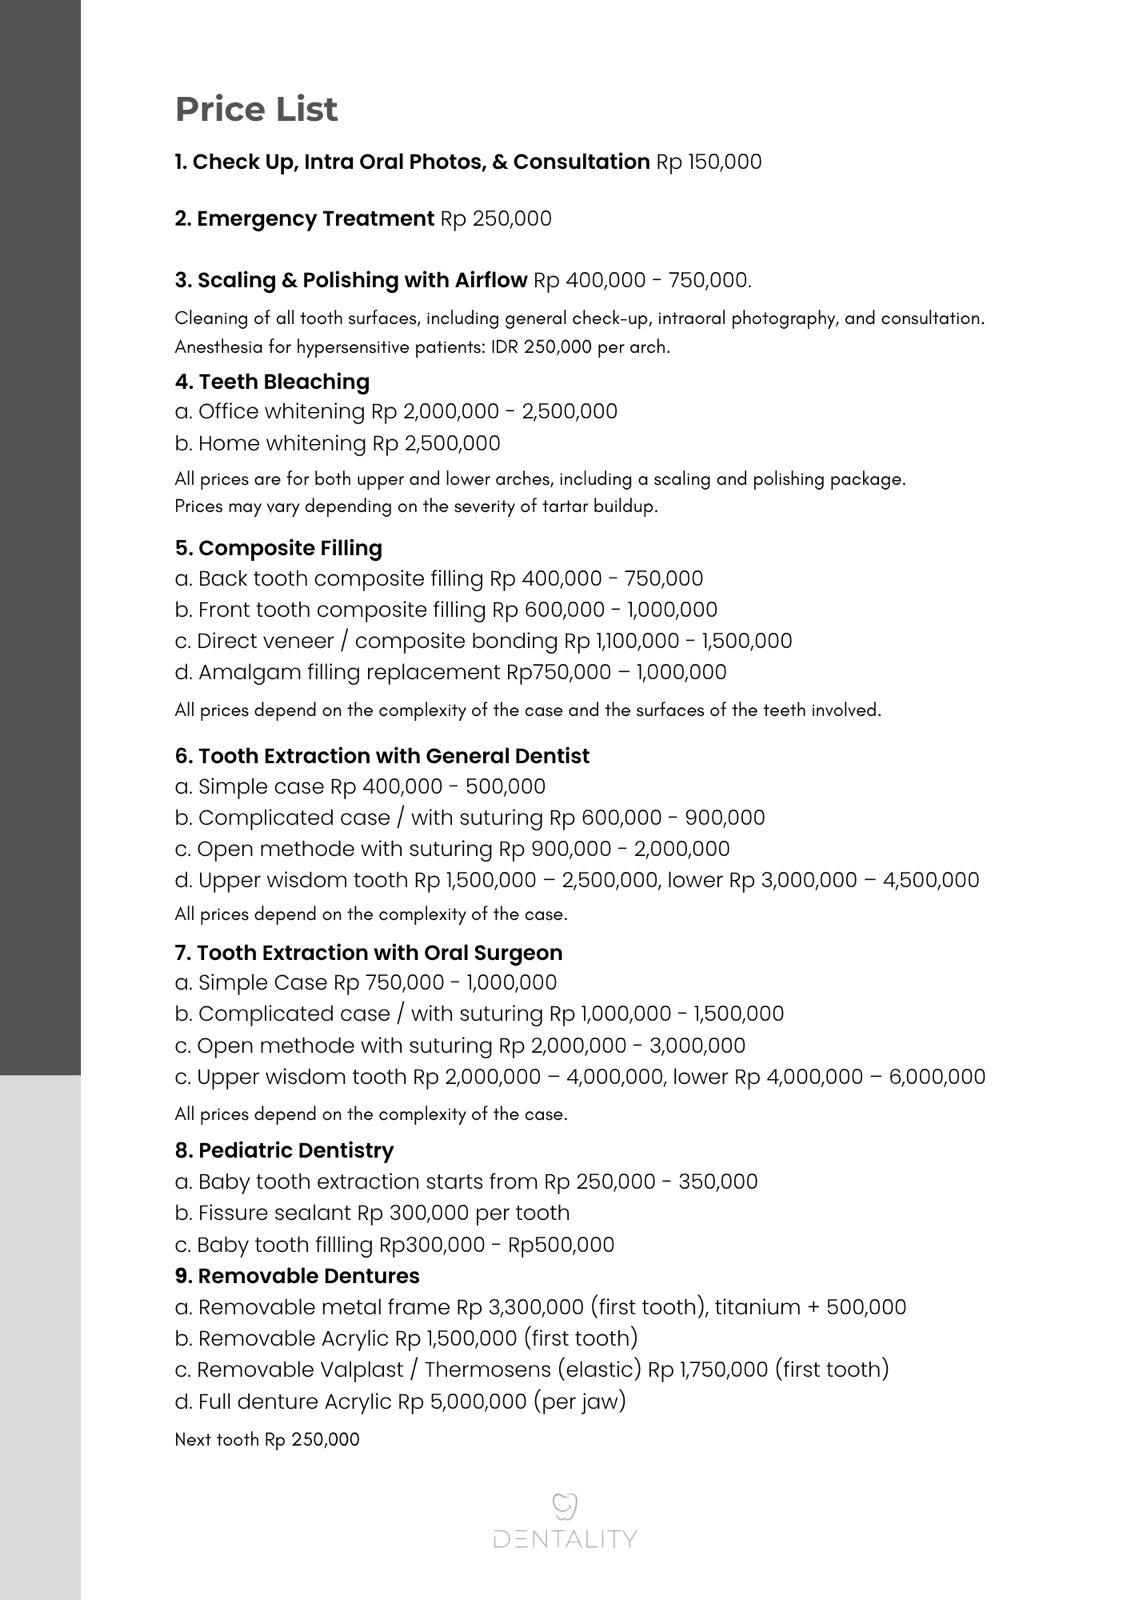

Semuanya, dari scaling, whitening, tambal gigi, hingga implant dan crown gigi.